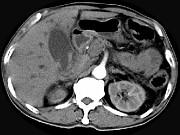

问题 男,58岁,患者右季肋区疼痛,皮肤黄染,可触及肿大胆囊,B超提示胆囊颈部肿块影,CT所见如图,最可能的诊断是()

选项 A.胆囊息肉 B.胆囊癌 C.胆囊黄色肉芽肿 D.慢性胆囊炎 E.胆囊腺肌增生症

答案 B